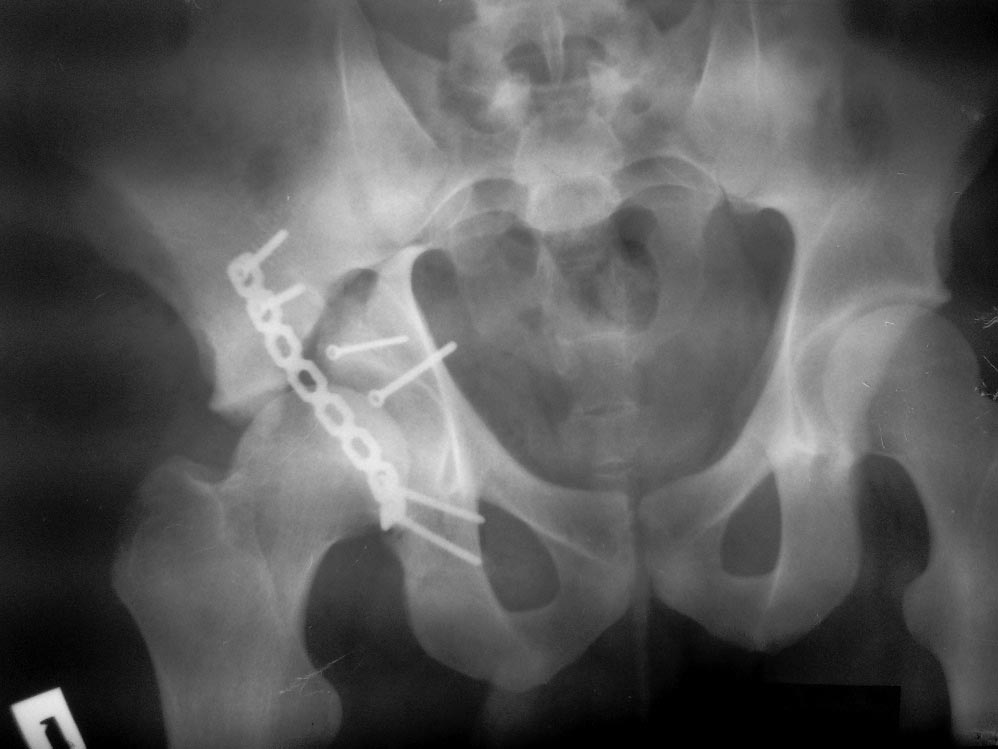

Уважаемые коллеги! Пациент 19 лет, ДТП в сентябре 2012 г, оперирован

поэтапно в др. клинике. В сентябре пациенту первым этапом была проведена

операция МОС лодыжек правой голени, МОС правой бедренной кости. Через 2

недели была проведена операция МОС костей таза и открытое

устранение вывиха правого бедра. Повторная операция реостеосинтез костей

таза была проведена через 1 месяц после первичной. Дз: задний вывих

правого бедра (сроки -3 месяца).

Асептический некроз головки правой бедренной кости. Неконсолидирующийся

перелом средней трети правой бедренной кости, неправильно

консолидирующийся перелом лодыжек правой голени с подвывихом стопы

кзади, передняя медиальная нестабильность правого К/С.

Сгибательно-приводящая контрактура правого Т/Б сустава,

сгибательно-разгибательная контрактура правого К/С, эквинусная установка

в правой стопе на фоне пост-операционного пареза Жду Ваших рекомендаций

по плану лечения.